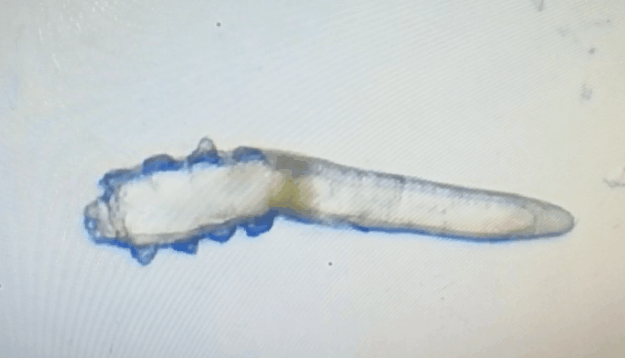

廈門(mén)眼科中心眼表及角膜病專(zhuān)家商旭敏博士指出:蠕形螨中的毛囊蠕形螨和皮脂蠕形螨可寄居于人體。在眼部,毛囊蠕形螨常寄居于睫毛囊,而皮脂蠕形螨多寄居于眼瞼皮膚的皮脂腺和瞼板腺。蠕形螨瞼緣炎是蠕形螨感染瞼緣所致的慢性炎性反應(yīng)性疾病,主要累及瞼緣皮膚、睫毛囊和腺體以及瞼板腺,以眼癢、眼異物感、眼干、瞼緣充血、鱗屑及睫毛根部袖套狀分泌物等為典型臨床表現(xiàn),嚴(yán)重者可引起結(jié)膜及角膜并發(fā)癥,該病可能具有一定的傳染性。

蠕形螨的危害不容小覷?。?!

蠕形螨會(huì)引起睫毛異常,引發(fā)瞼緣炎性反應(yīng),瞼板腺堵塞,引起結(jié)膜炎、角膜炎等并發(fā)癥,嚴(yán)重的話將發(fā)生角膜穿孔致視力損傷甚至失明。